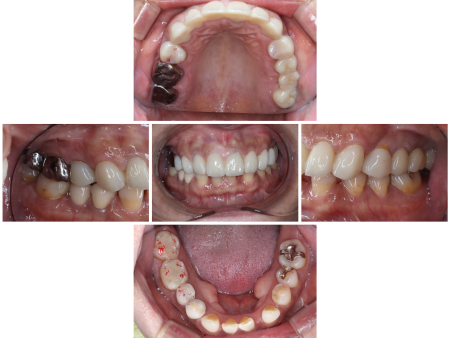

「上の前歯が痛い」とご相談いただきました。

拝見したところ、右上前歯2本(中切歯/1番、側切歯/2番)の根の周りに炎症が認められ、痛みの原因になっていました。

しかし今回の患者様の場合、前歯のすり減りが激しく噛み合わせが低くなっていたため、このままの状態で治療を進めると被せ物を装着した歯が下の前歯に強く当たり過ぎて、被せ物や土台、歯の根も割れてしまう恐れがあります。

また、全体的に歯の着色も見られ、詳しく調べてみたところ、歯の形成期にテトラサイクリン系の抗生物質を大量に服用したことが原因で歯が変色してしまう「テトラサイクリン歯」であることもわかりました。

根の炎症を改善するために右上前歯2本の根管治療を行ったあと、上の歯すべて(右の第2大臼歯/7番〜左の第2大臼歯)に強度のある被せ物を装着する治療を提案しました。

右上前歯2本だけでなく、上の歯全体に新たな被せ物を入れることで、噛み合わせが全体的に上がり被せ物や歯の根が割れるリスクを回避できます。また、白くそろった歯の色に仕上がることもお伝えしたところ、同意いただきました。

まずは右上前歯2本に精密な根管治療を行うために、治療する歯のみをゴムのシートで保護する「ラバーダム防湿」を施し、唾液や細菌が入らないよう清潔な環境を整えてから細部まで丁寧に処置しました。

その後、上の歯すべてに仮歯である「プロビショナルクラウン」を作製し、噛み合わせや歯ぎしりをした際の歯の当たり具合などをしっかり確認して形を整えたあと、プロビショナルクラウンの形に応じて最終的な被せ物を装着しています。

被せ物については、口を開けた時に特に目立つ前歯6本(右上犬歯/3番~左上犬歯)は患者様と相談した結果、耐久性と審美性に優れた自費の被せ物「ジルコニアクラウン」を選択されています。

欠損していた左上奥歯(第2大臼歯/6番)には両隣の歯を土台にして橋渡しのように被せ物を入れる保険の「ブリッジ」がもともと入っていましたが、今回前歯同様、ジルコニアクラウンでやり替えを行いました。

最後に、左右上の歯2本(第1小臼歯/4番)は保険の白い被せ物「CAD/CAM冠」を、右上奥歯2本(第1大臼歯、第2大臼歯)も保険の金属製の被せ物をそれぞれ装着し、治療を終了しています。